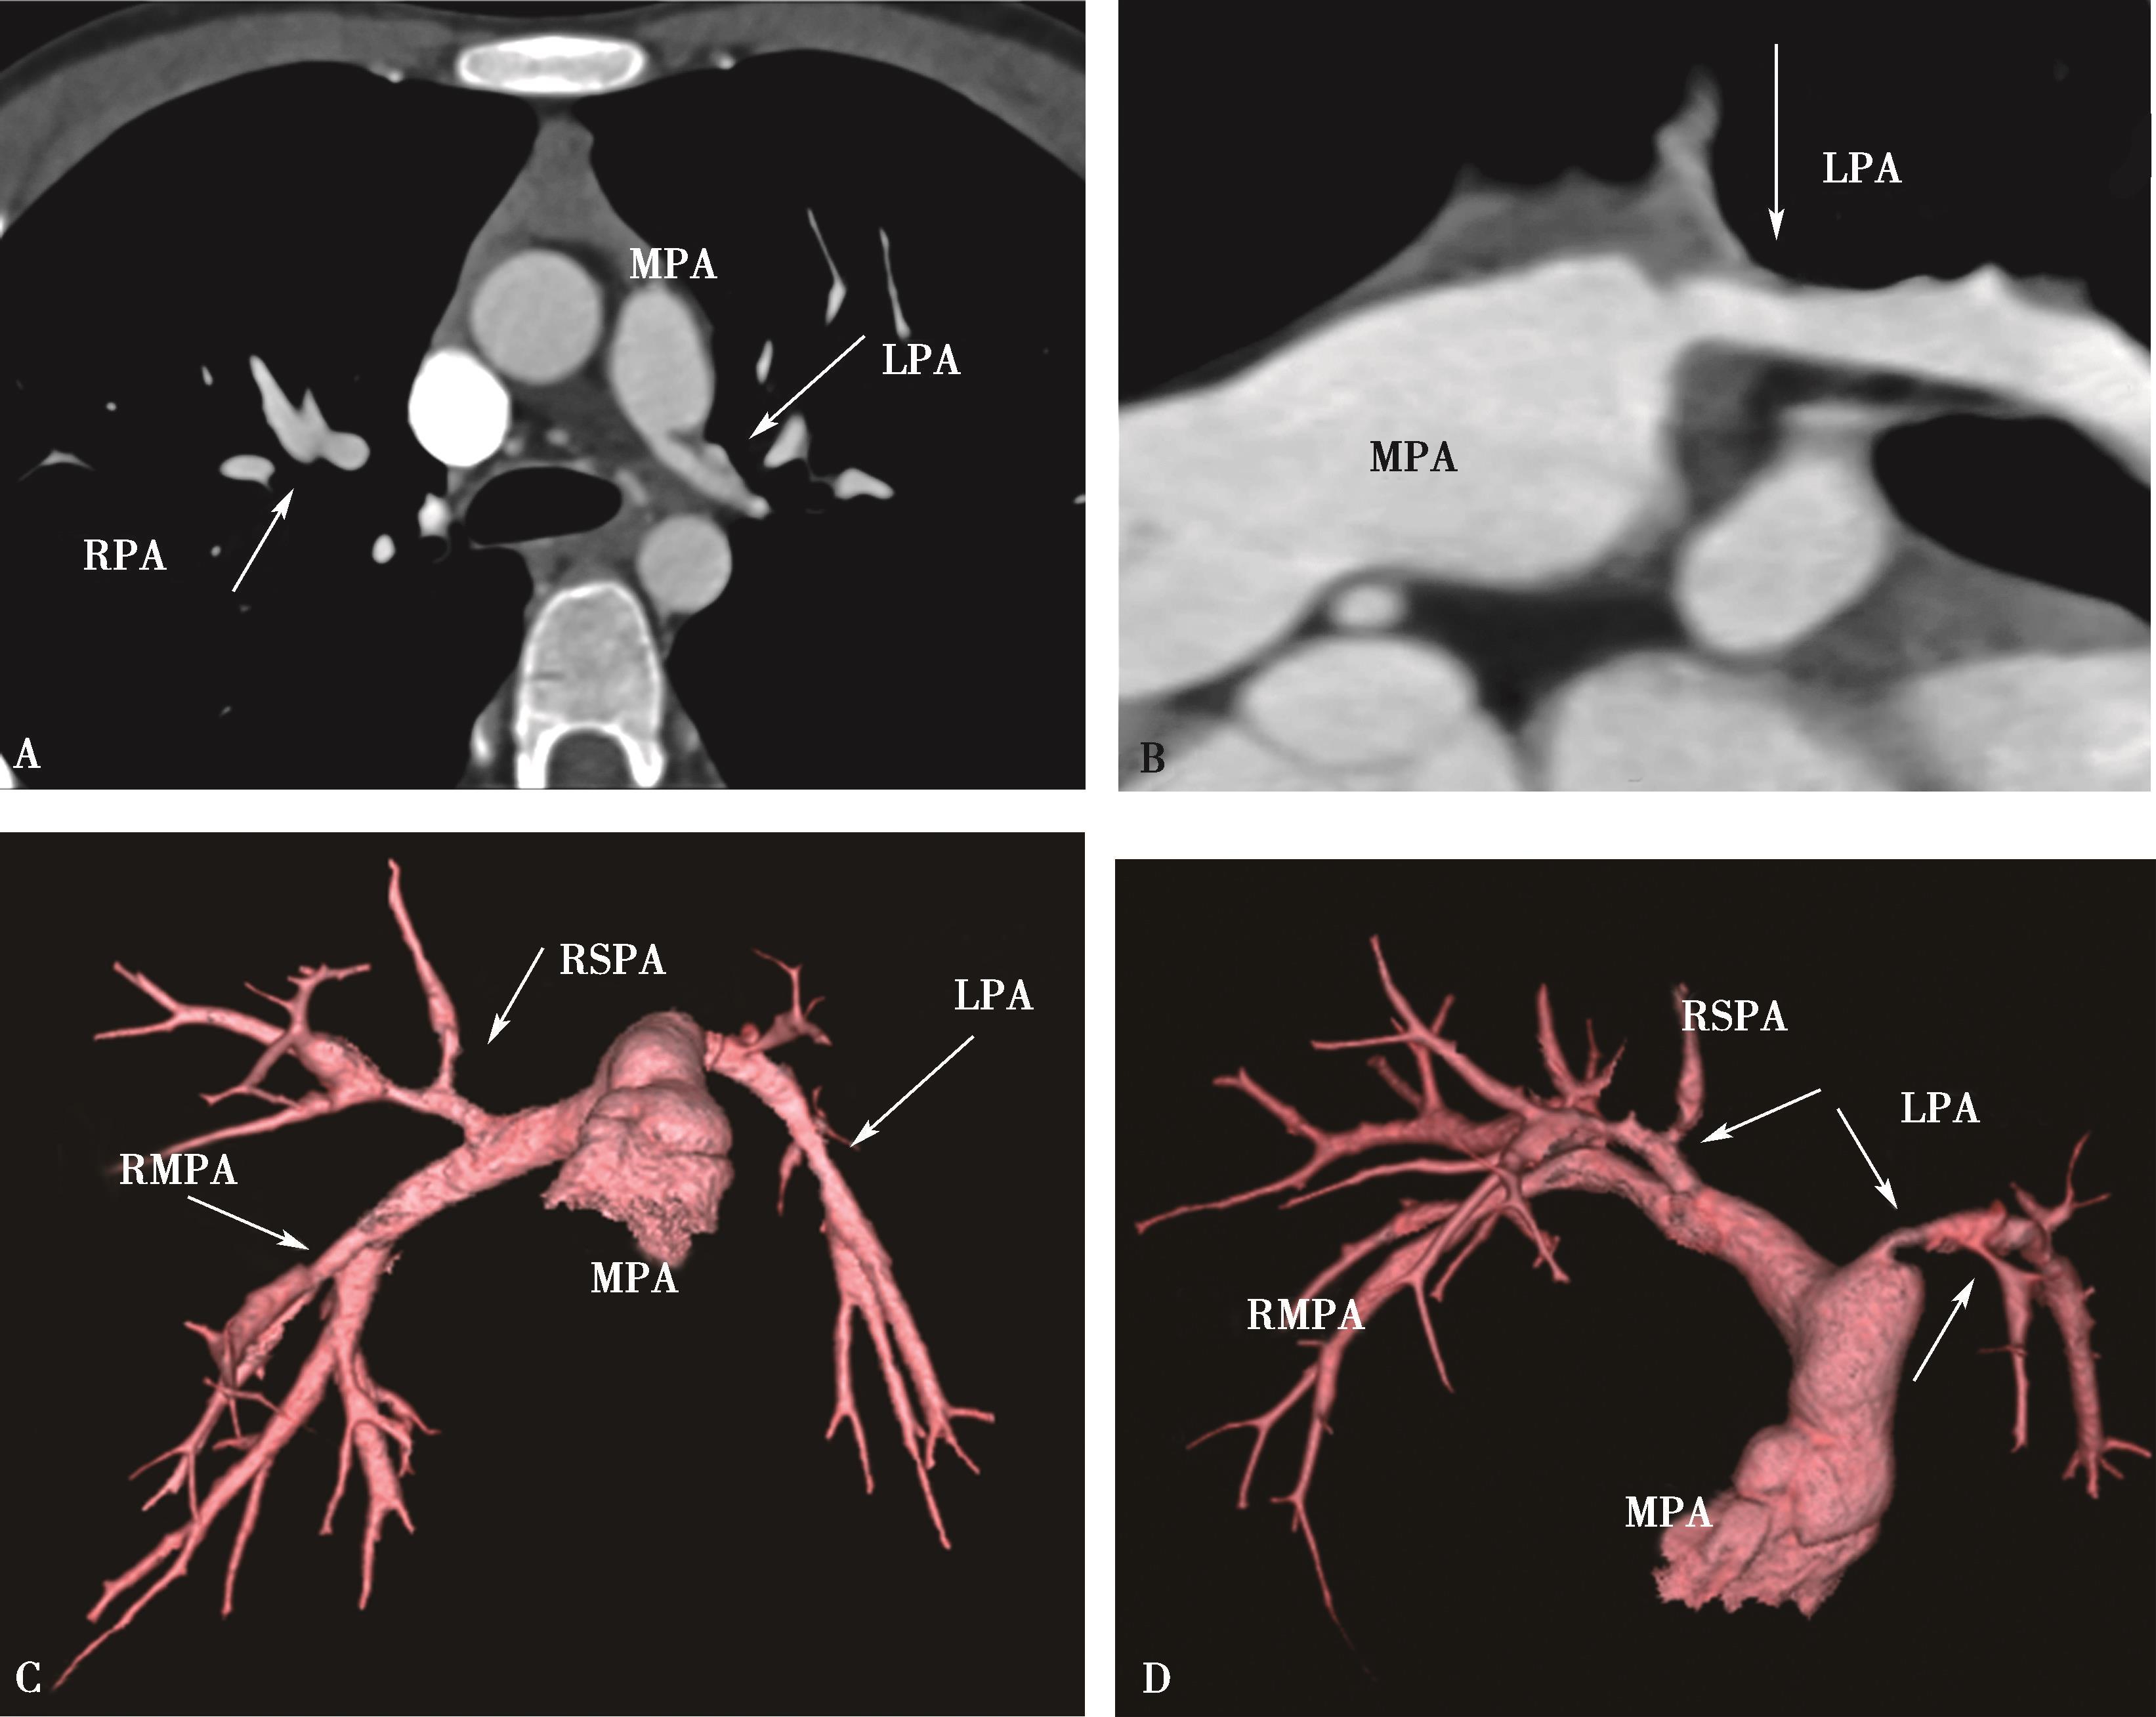

图8-2-1 肺动脉容积再现(VR)

正常肺动脉:A.冠状位;B.背面观;C.左前斜位;D.右前斜位